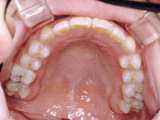

症例4:上顎前突(出っ歯)

治療前

治療後